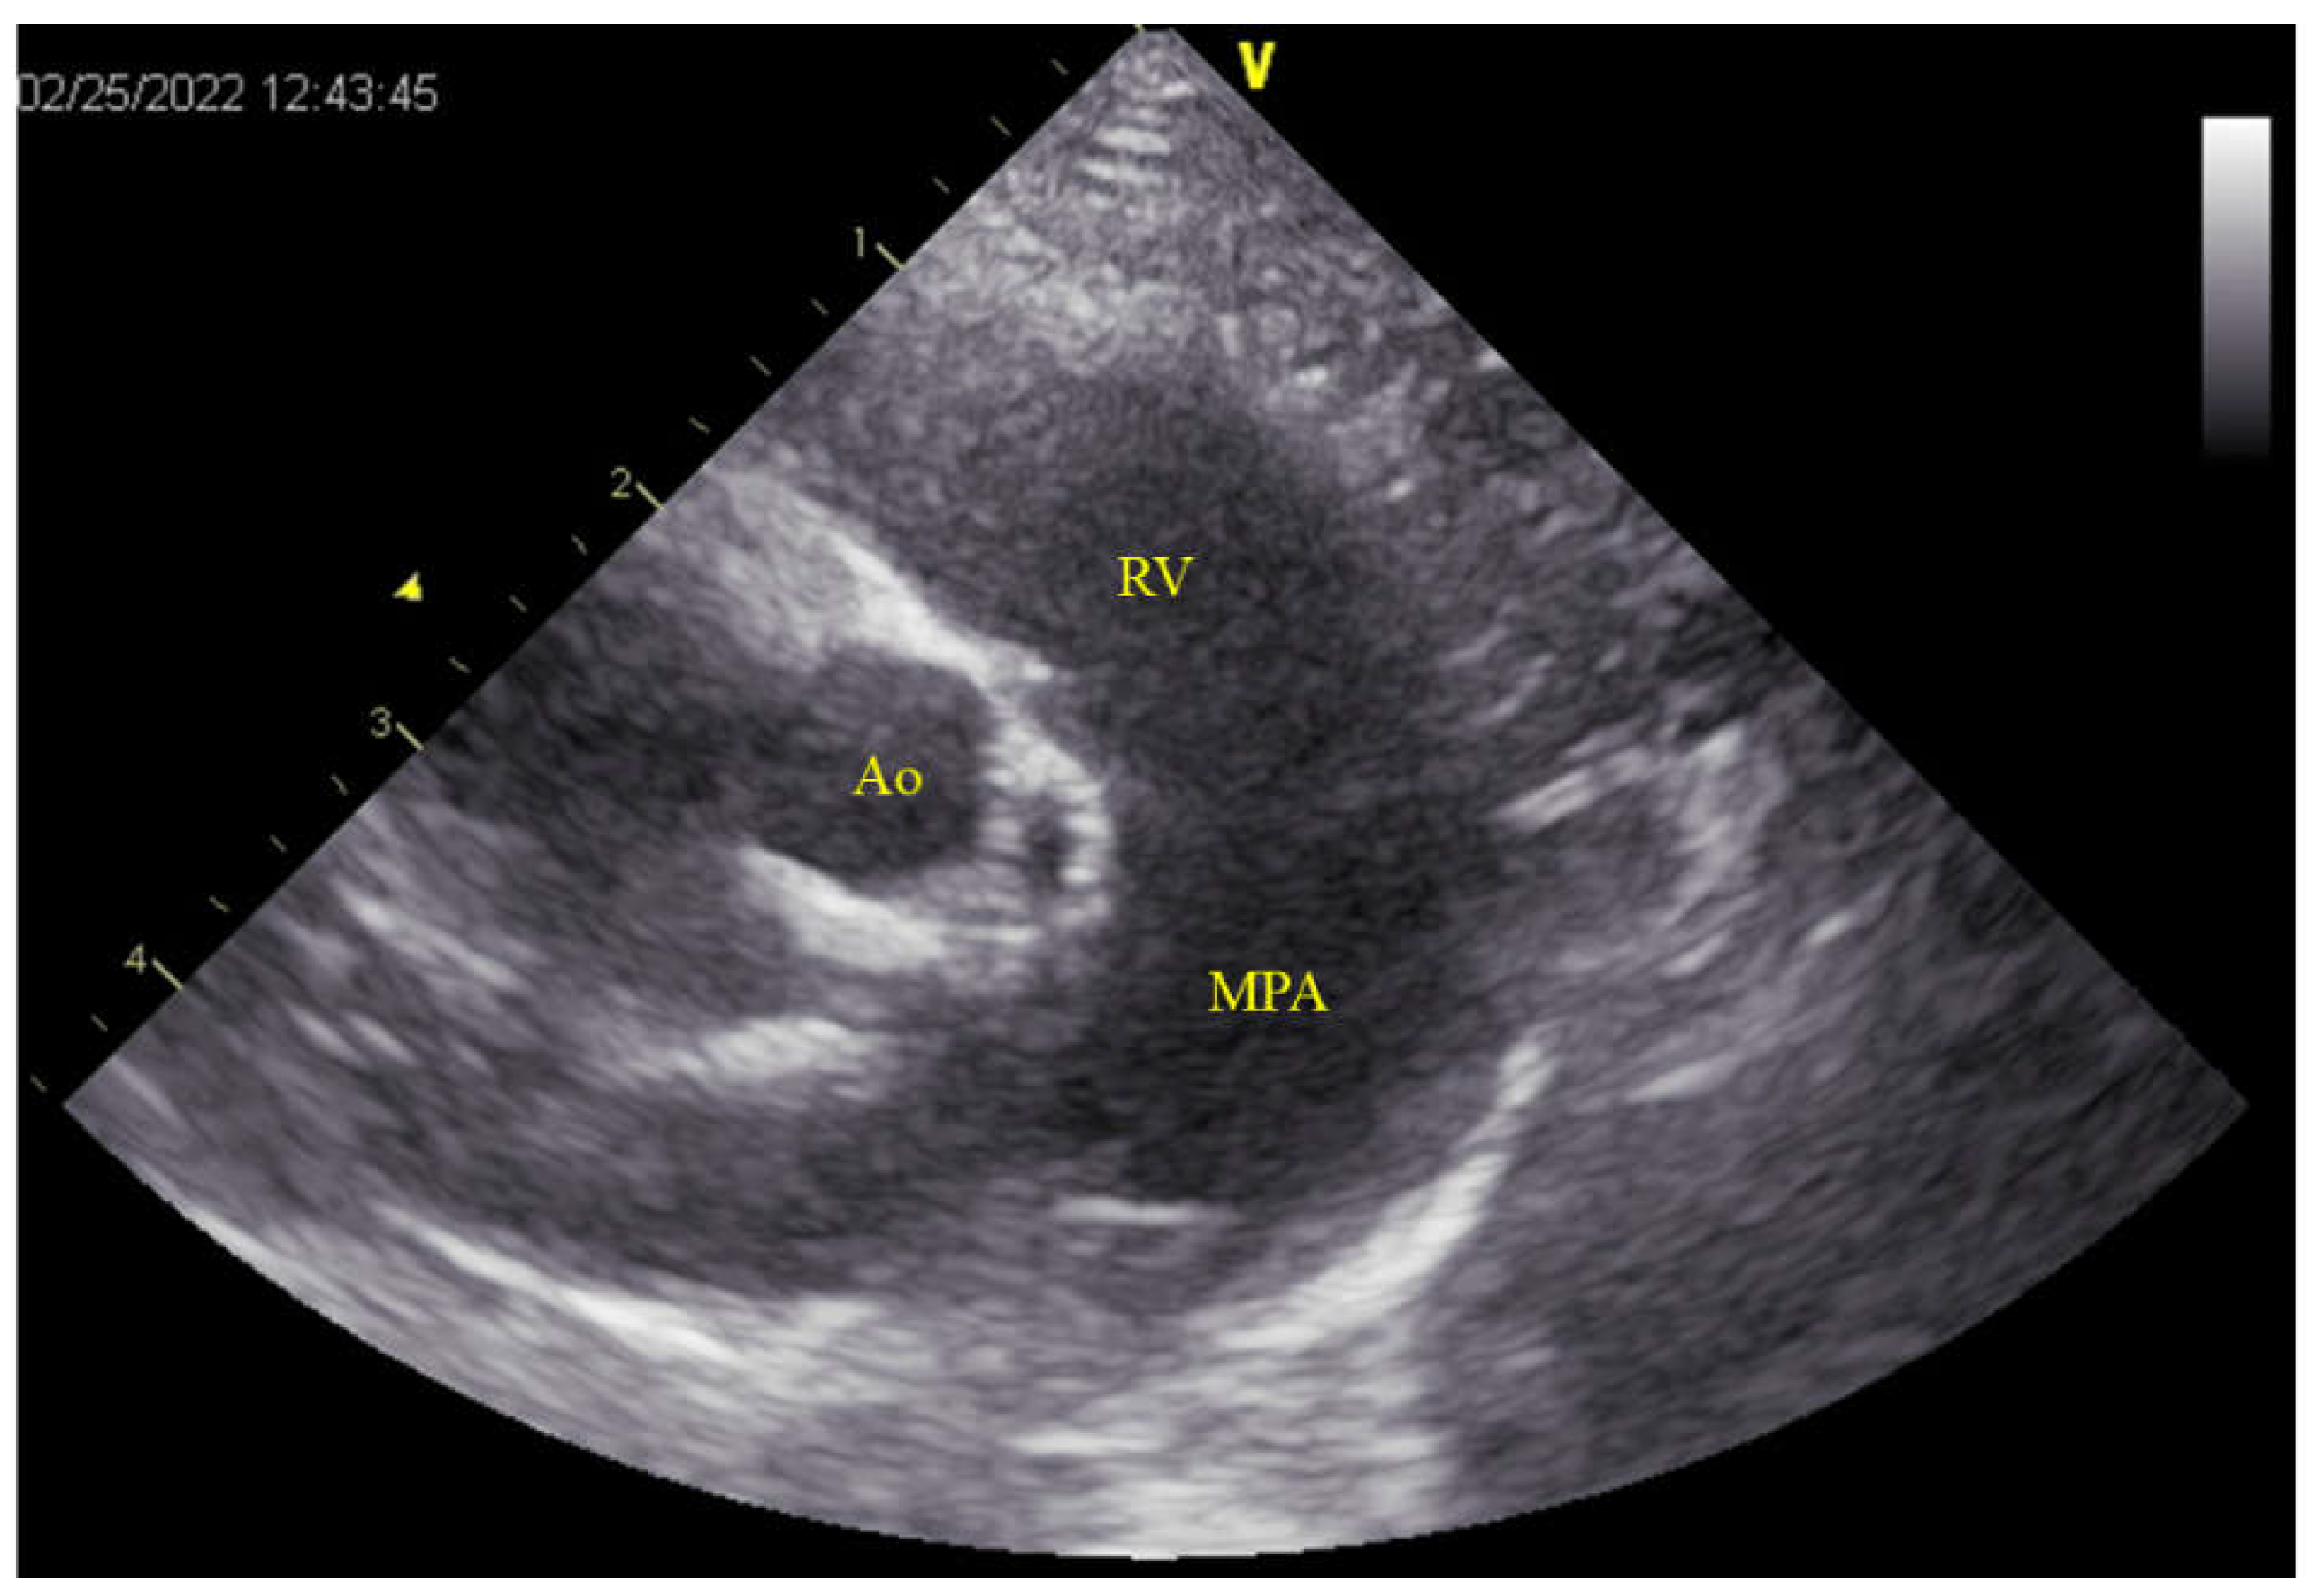

After cardiac arrest was induced, the main pulmonary artery was incised, and the pulmonary valve was incised to the right ventricle at the commissure to expose the ventricular septum. This revealed an elliptical defect surrounded by muscular tissue, measuring 9 mm in length and approximately 2–3 mm in width (Figure 3A). The full extent of the defect was visualized by inserting a right-angle clamp into the defect and pulling it towards the operator. The rim of the defect was sutured using six double-armed sutures with polypropylene pledgets (Oval-M; Matsudaika Inc., Tokyo, Japan). A patch (Nippon Becton Dickinson Company, Ltd., Tokyo, Japan) was used to close the defect, which was tailored to fit the size of the hole. Double-armed needles previously sewn into the rim were then threaded through the circular patch in sequence, and closure was completed once it was confirmed that no blood had leaked from the left ventricle (Figure 3). Subsequently, blood was evacuated from the left atrial vent cannula, and the pulmonary artery and right ventricle were continuously sutured using 6-0 polyvinylidene fluoride sutures. The right atrium was similarly sutured continuously, and upon release of the aortic cross-clamp, spontaneous beating of heart resumed. Partial cardiopulmonary bypass continued until the patient was rewarmed to 36.5 °C. The total aortic cross-clamp time was 56 min and cardiopulmonary bypass duration was 105 min. Subsequently, a chest drain was placed and the chest was closed in the standard manner. Postoperative pain was managed with fentanyl (2 microg/kg/h) administration continuously for 24 h.

Figure 3. Intraoperative findings of the VSD. (A) The MPA is incised, and an incision from the commissure of the PV to the RV reveals a VSD measuring 9 mm in length and 2–3 mm in width (yellow arrow-head). The defect is observed on the RV side of the PV. (B) The VSD is closed by using a patch (yellow arrow). MPA: main pulmonary artery; PV: pulmonary valve; RV: right ventricle; VSD: ventricular septal defect.